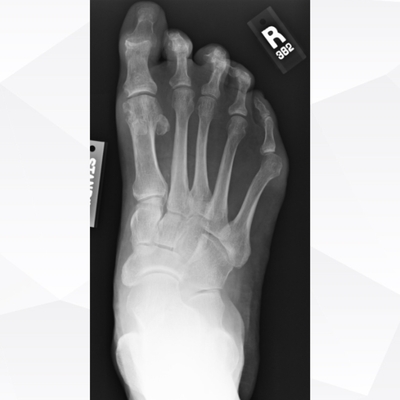

Click on an image below to view more info.